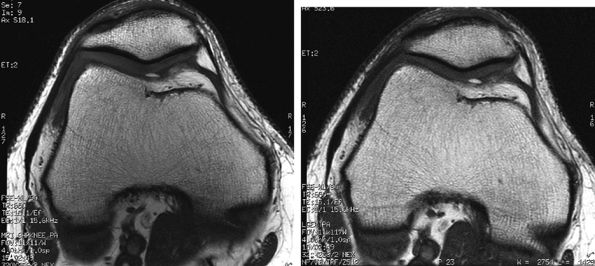

FIGURE 1.3 ● Total knee arthroplasty with synovitis (arrows). Acquired at 1.5 T. Use of an RBW of 83.3 kHz results in limited metallic susceptibility artifact.

|